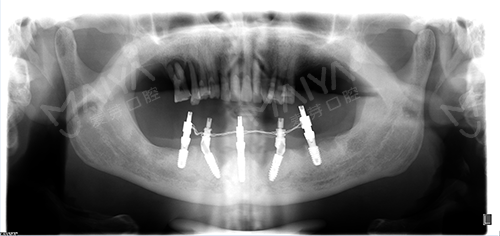

麦芽数字生物种植技术——5颗钉种出半口牙,种牙当天用!

麦芽口腔数字化种植牙中心,通过德国KAVO锥形束CT口腔数据检测,制定种植牙导板,告别传统栅栏式种牙,麦芽独家定制all-on-5方案,无需切开牙龈,1小时七旬老汉长出半口新牙。省下1/3费用。